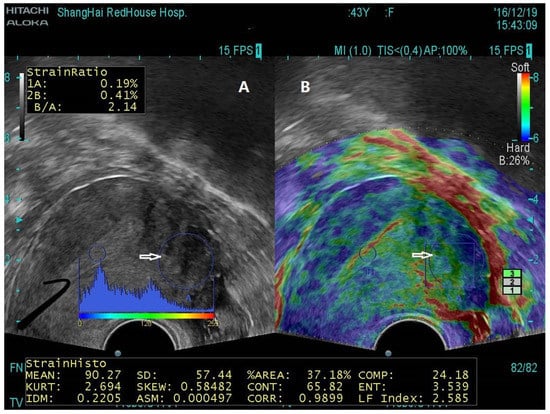

- Liu, X.; Ding, D.; Ren, Y.; Guo, S.W. Transvaginal Elastosonography as an Imaging Technique for Diagnosing Adenomyosis. Reprod. Sci. 2018, 25, 498–514. [Google Scholar] [CrossRef]

- Sasaran, V.; Turdean, S.; Marginean, C.; Gliga, M.; Ilyes, L.; Grama, O.; Puscasiu, L. Transvaginal Ultrasound Combined with Strain-Ratio Elastography for the Concomitant Diagnosis of Uterine Fibroids and Adenomyosis: A Pilot Study. J. Clin. Med. 2022, 11, 3757. [Google Scholar] [CrossRef]

- Sasaran, V.; Turdean, S.; Gliga, M.; Ilyes, L.; Grama, O.; Muntean, M.; Puscasiu, L. Value of Strain-Ratio Elastography in the Diagnosis and Differentiation of Uterine Fibroids and Adenomyosis. J. Pers. Med. 2021, 11, 824. [Google Scholar] [CrossRef] [PubMed]